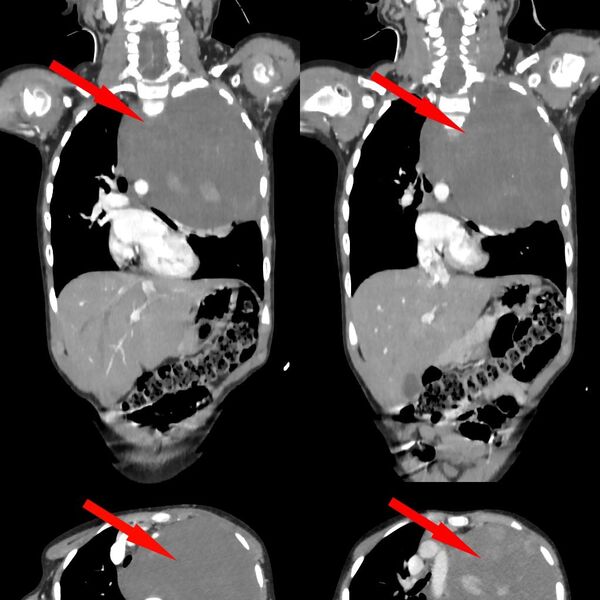

Родители показали дочь врачам, когда заметили у нее небольшую припухлость в области шеи. Специалисты по месту жительства выявили огромное новообразование размером со страусиное яйцо, которое сдавливало сердце и легкое. Сквозь ткань опухоли проходили крупные сосуды: «позвоночная артерия, питающая головной мозг, и подключичная артерия с ее ветвями, питающая левую руку». После телемедицинской консультации ребенка направили в Москву.

«Учитывая гигантский размер опухоли и ее расположение вблизи множества жизненно важных структур, мы использовали расширенный доступ по типу «раковины моллюска». Он предполагает рассечение не только межреберного промежутка, но и самой грудины, что позволяет «раскрыть» грудную клетку, как раковину», — рассказал заведующий отделением реконструктивной и восстановительной хирургии грудной полости РДКБ, к.м.н. Евгений Андреев об операции.

Специалист отметил, что благодаря слаженной и кропотливой работе медикам удалось удалить новообразование единым блоком, не нарушив целостность.